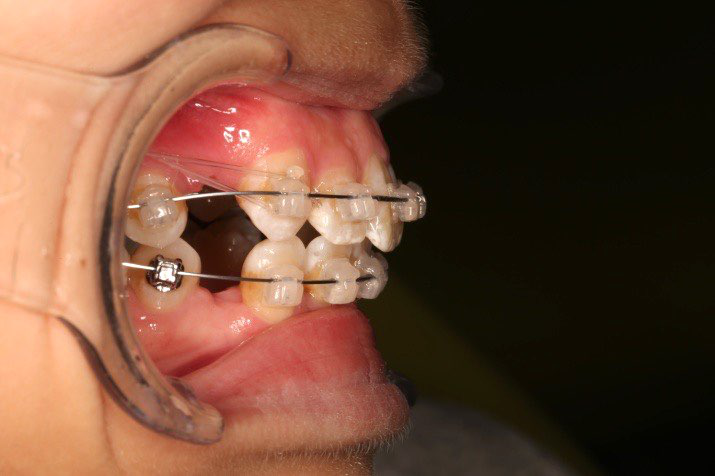

10 M after Post-Tx

10 M after Post-Tr

2019.08.06  术后  10个月复查

治疗后评价

宏观评价:面部对称,面下三分一比例协调,上下唇凸度正常,上颌牙列内收转矩控制良好,下颌后缩改善,颏唇沟变得更加柔和,术后达到基本直面型。

迷你观评价:上下牙齿中线与面中线对齐,笑弧协调,微笑时牙龈暴露量正常,微笑时横向正常,左右唇基本对称。

微观评价:牙齿整齐,咬合关系良好,上下前牙转矩及突度控制良好,磨牙关系I类,尖窝咬合关系良好,OB,OJ正常。